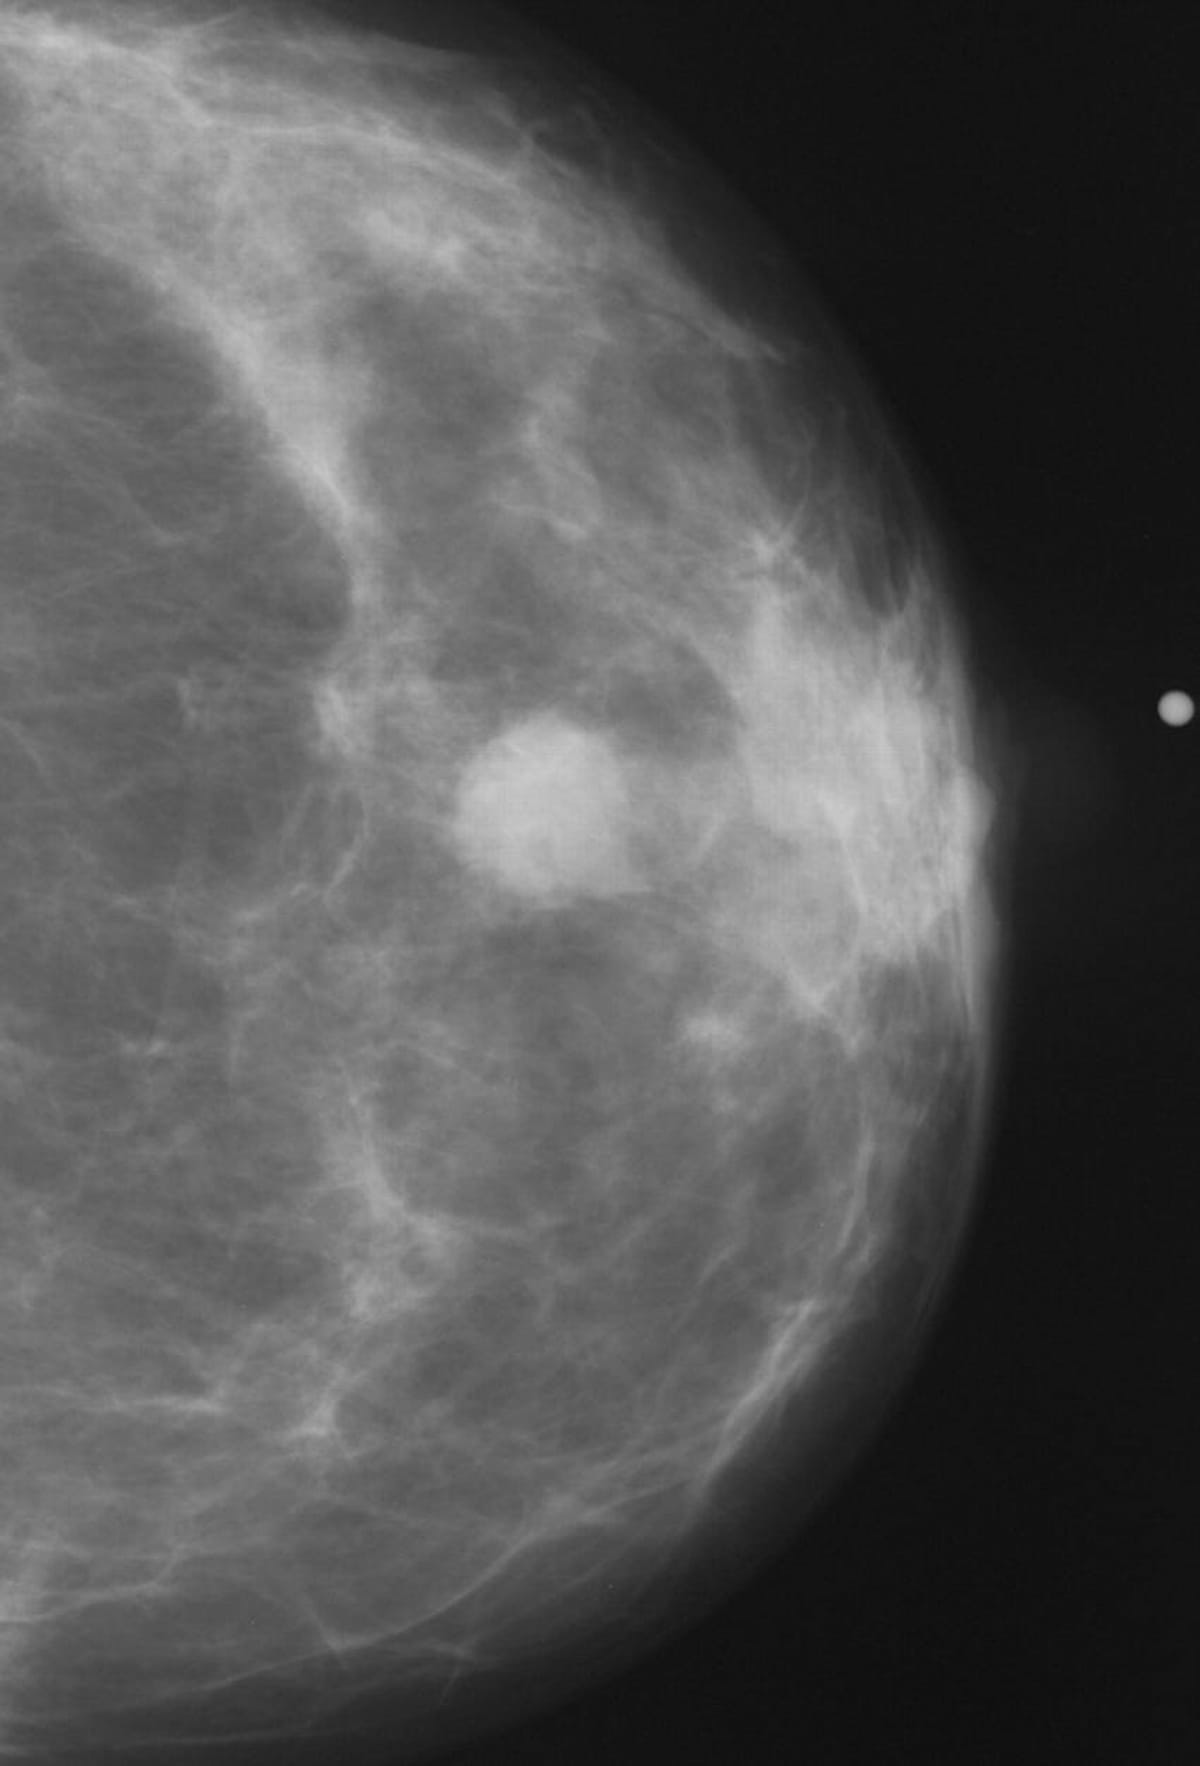

Here one can see an abnormal mammogram finding. Breast cancer survival rates ranged between 82.7 to 86.9 percent for women who participated in the five most recent mammography screenings prior to breast cancer diagnosis, according to new research presented at the annual RSNA conference.

The researchers found that breast cancer survival rates ranged between 82.7 to 86.9 percent for women who participated in the five most recent mammography screenings prior to breast cancer diagnosis. In contrast, women who did not have any of those screenings prior to diagnosis had a survival rate between 59.1 and 77.6 percent, according to the study authors.

In comparison to women with no mammography screening, the researchers emphasized that adherence to the five mammography screenings prior to diagnosis reduced the risk of breast cancer mortality by 72 percent.